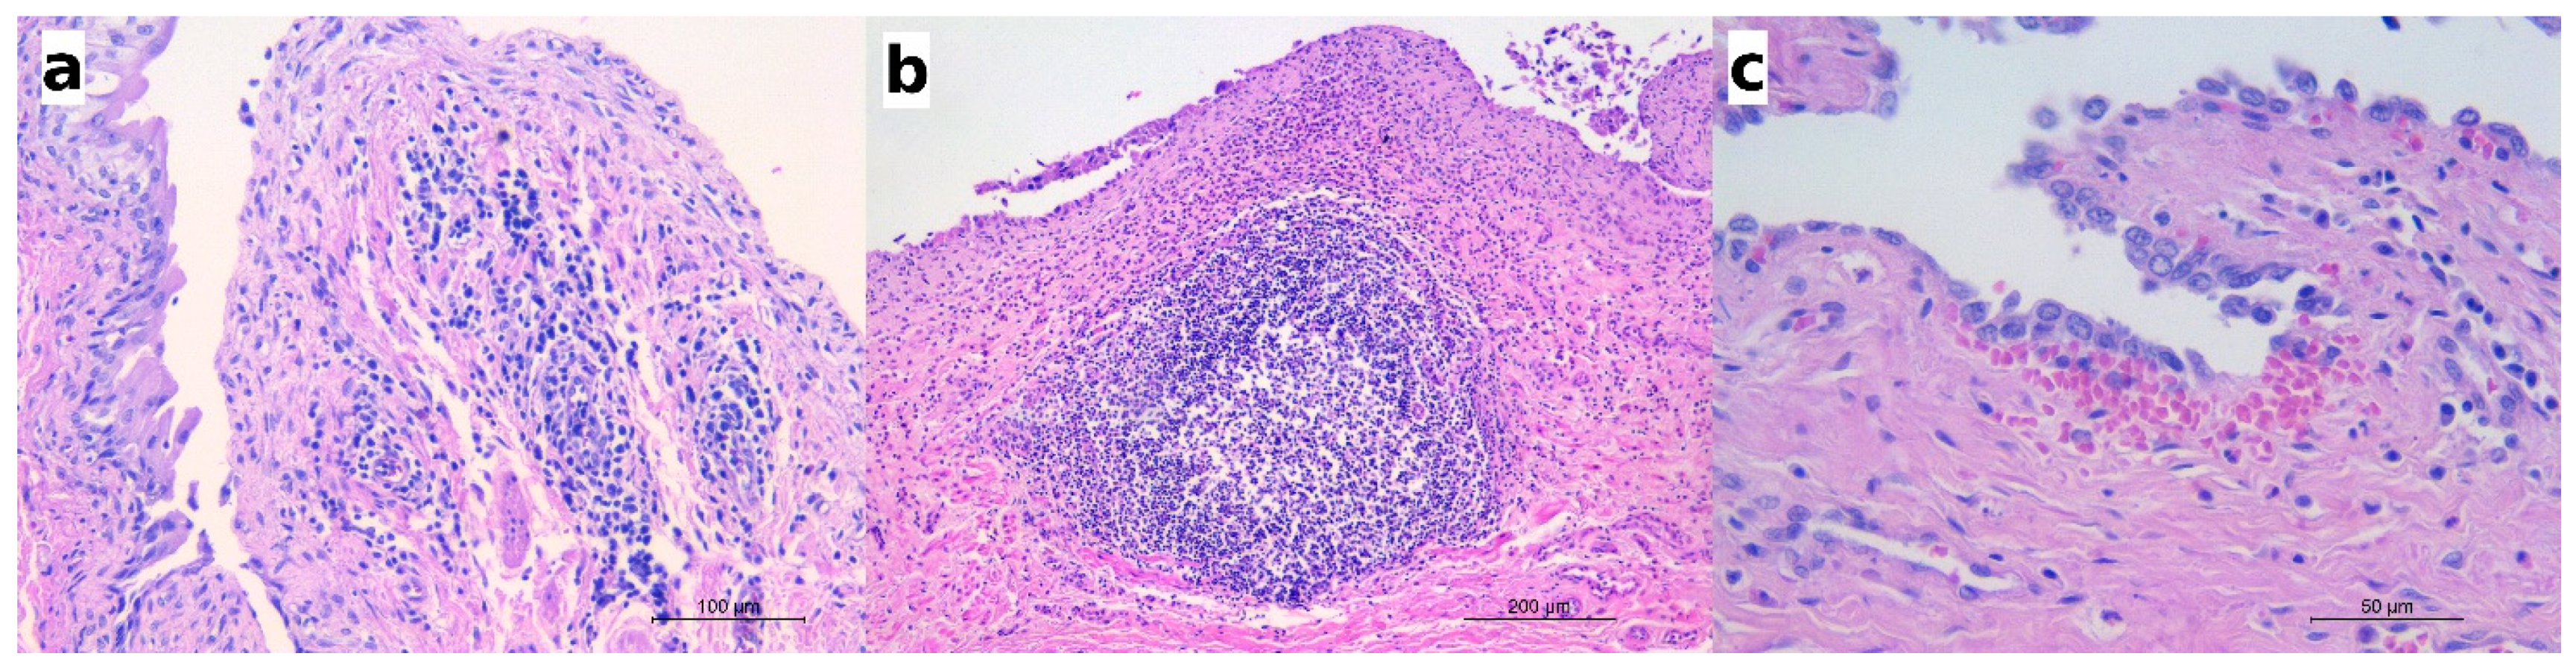

2.3. Histology